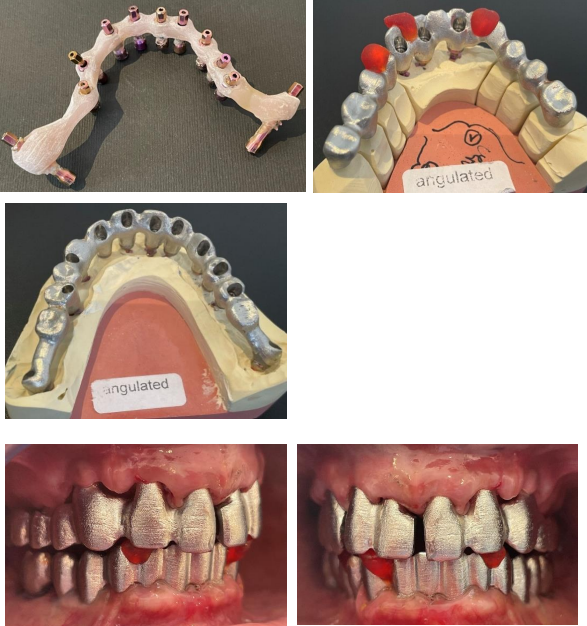

After the surgery the impression was taken immediately with screwed transfers and a temporary bridge was made at chairside. Fig 8

Figure 8: Laboratory steps - screwed transfers and aesthetical trial.

The transfer key was tried in on the second appointment to check the impression, an aesthetical trial was also done. After validation third appointment was fixed to try in the frame Fig  9

A metal ceramic bridge was fabricated after frame try-in. Three weeks after the beginning of the treatment, the gum has healed nicely, bridge was screw-retained with angulated screw channels so as to get a perfect fit fig 10.

Figure 10